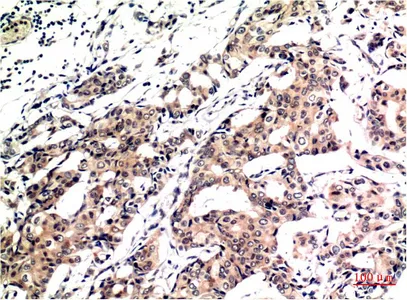

CDX2(14H6)Mouse Monoclonal Antibody

Cat: AMM08595

Size1:50μL Price1:$118

Size2:100μL Price2:$220

Size3:200μL Price3:$380

Application:WB,IF-P,IF-F,ICC/IF,IHC-P

Reactivity:Human,Mouse,Rat

Conjugate:Unconjugated

Optional conjugates: Biotin, FITC (free of charge). See other 26 conjugates.

Gene Name:CDX2